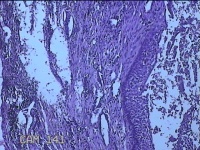

左上后牙根尖肿物

性别

男

年龄

42岁

临床诊断

慢性牙周炎

一般病史

左上后牙残根邀请拔除。

标本名称

大体所见

灰白暗红色肿物1.5x0.8x0.3cm一个,表面光滑,切开肿物呈囊性,囊内有大量脓液,囊壁厚0.2ml,另有牙齿1.5x0.8x0.7cm一颗。